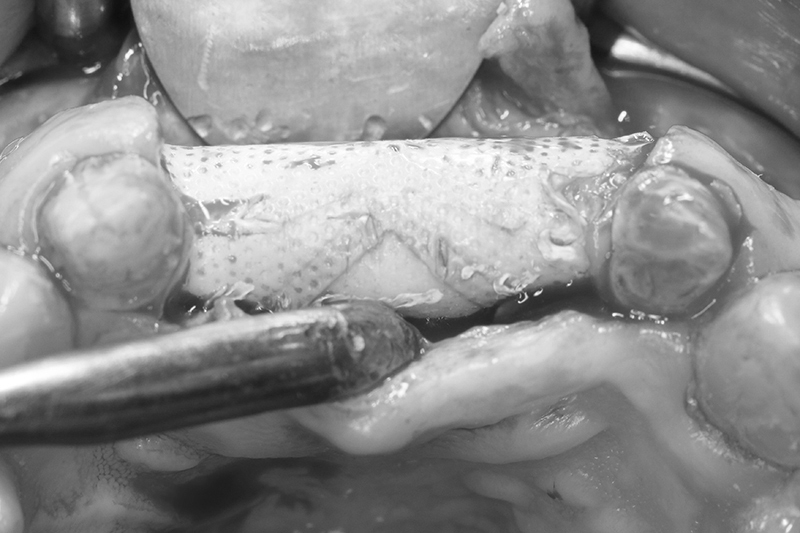

取出的舊有one piece植體,舊式植體。